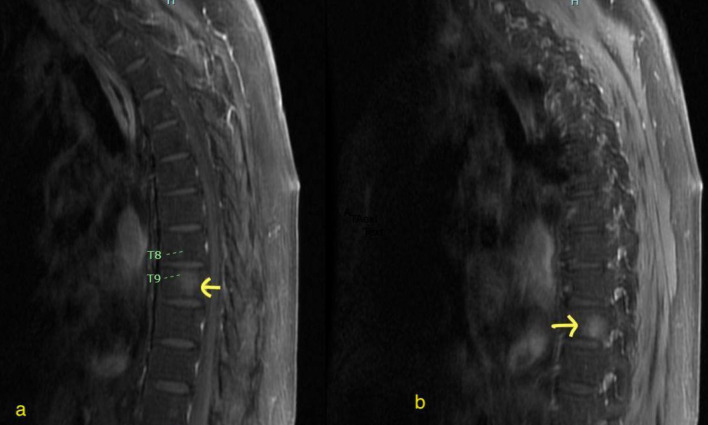

Tyrosine kinase inhibitors (TKIs) have changed the prognosis of Philadelphia-positive B-cell acute lymphoblastic leukemia (ALL); however, relapsed and refractory disease after multiple TKIs continues to be a clinical challenge. Brexucabtagene autoleucel (brexu-cel) is a novel FDA-approved therapy for relapsed and refractory ALL. Given the lengthy manufacturing time, bridging therapy is commonly employed prior to brexu-cel. Here we describe a case of a 75-year-old Hispanic male patient with relapsed/refractory Philadelphia-positive B-cell ALL with extramedullary disease involving abdominal lymph nodes and skin. He was initially treated with chemotherapy in combination with imatinib, and later received dasatinib and subsequently blinatumomab and nilotinib. As the patient progressed, he received ponatinib with low-dose salvage chemotherapy and did not show kinase domain mutation. In a final effort, a novel combination of ponatinib with asciminib was used as a bridge therapy before brexu-cel and later as maintenance therapy after brexu-cel. This novel combination was able to control disease prior to brexu-cel for 2 months and maintained remission for at least 10 months. This report shows that the novel combination of ponatinib and asciminib is tolerable and effective as a bridge and maintenance therapy after brexu-cel.